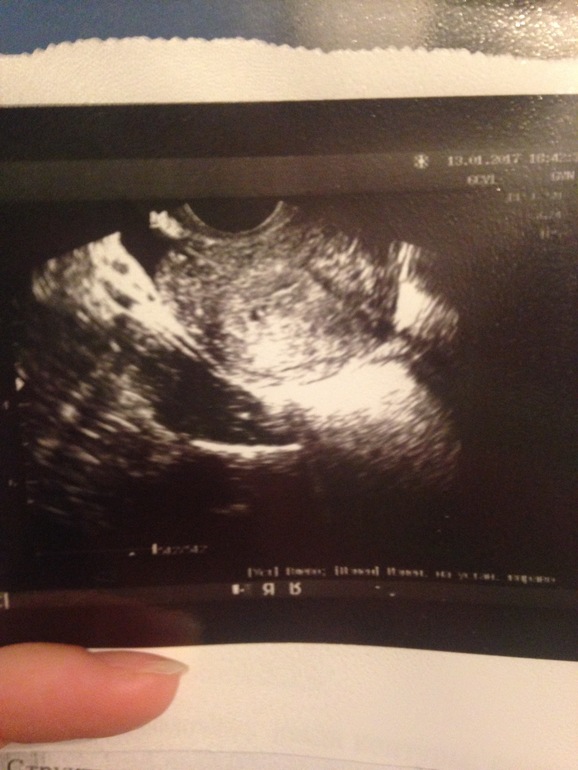

18дпо была на УЗИ, плодное яйцо 3 мм, хгч 2069

Сегодня узи подтвердило беременность на 18 дпо. Плодное яйцо 3мм) Желтое тело 22 мм, мешочка и эмбриончика пока не видно, но я уверена, что все отлично!!! Ждала бер больше полутора лет..правой трубы нет, так что слева Богу!!!.....

13.01.2017